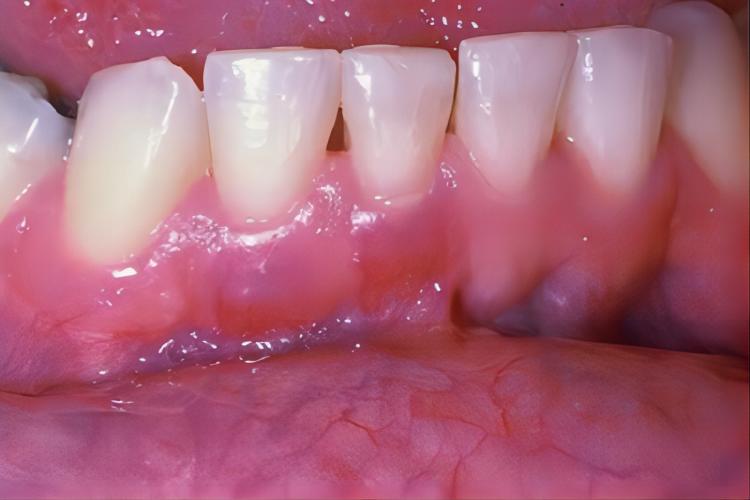

牙龈炎可导致口腔内下牙龈萎缩,伴有红肿,牙龈颜色为鲜红色,底部发黑。牙齿已经轻微露出牙根,刷牙或咬硬物可出现渗血或流血症状。

治疗牙龈炎导致的下牙龈萎缩,可采取多种措施。使用复方氯己定含漱液可以缓解牙龈炎症状,具有杀菌作用,可以减少牙龈炎引起的细菌感染,同时还能缓解牙龈肿痛和出血。进行定期洗牙也是重要的治疗方法。洗牙可以清除牙菌斑和牙结石,减少刺激牙龈的因素,促进牙龈健康。进行治疗时,应遵循专业医生的建议。